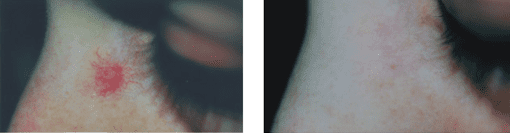

rosacea

Rosacea is a common disorder, causing a red facial rash affecting the cheeks and nose mostly, but also often the chin and lower forehead area.

The facial redness is caused by a combination of prominent blood vessels (telangiectasia) and background redness (erythema). In many cases there is also an eruption of acne-like lumps within the area of facial redness.

Rosacea can be treated successfully or greatly improved by Laser and IPL (Intense Pulsed Light) treatments, often in association with oral or topical treatments.